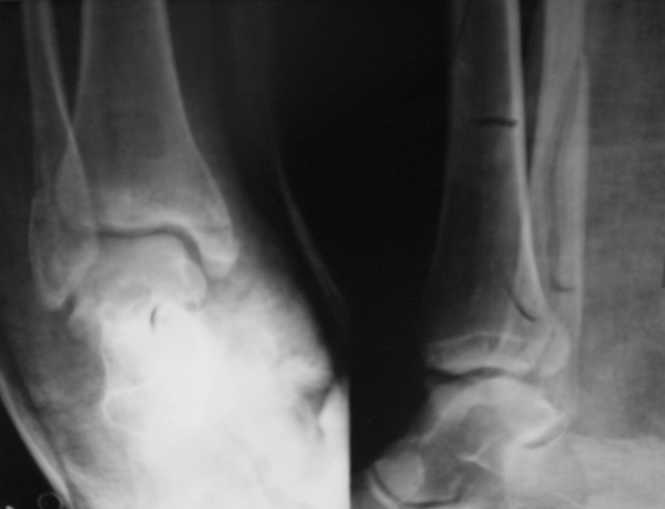

Стандартными снимками считается прямая, боковая и мортиз!!!, а так трудно гадать, насколько потеря длины малоберцовой. На боковом снимке не сопоставленный перелом медиальной лодыжки и перелом заднего края без смещения.

Ув. коллеги. Мы считаем, что синтезировать необходимо медиальную лодыжку, она ротирована. Малоберцовую кость лучше не трогать. Довольно травматично будет, фрагменты неплохо стоят. И то, оперировать медиальную лодыжку где-то в трехнедельном сроке, чтобы малоберцовую кость не развалить. Мнений много, мы благодарны за участие.

Очень жаль, что Вы так считаете и не прислушались к мнениям уважаемых коллег. Проблема этого голеностопного сустава не в "висячей" внутренней лодыжки, а ротированной и, возможно, укороченной малоберцовой кости. На снимках подвывиха как-буд-то бы нет, но таран ротирован и это в дольнейшем будет причиной раннего артроза.